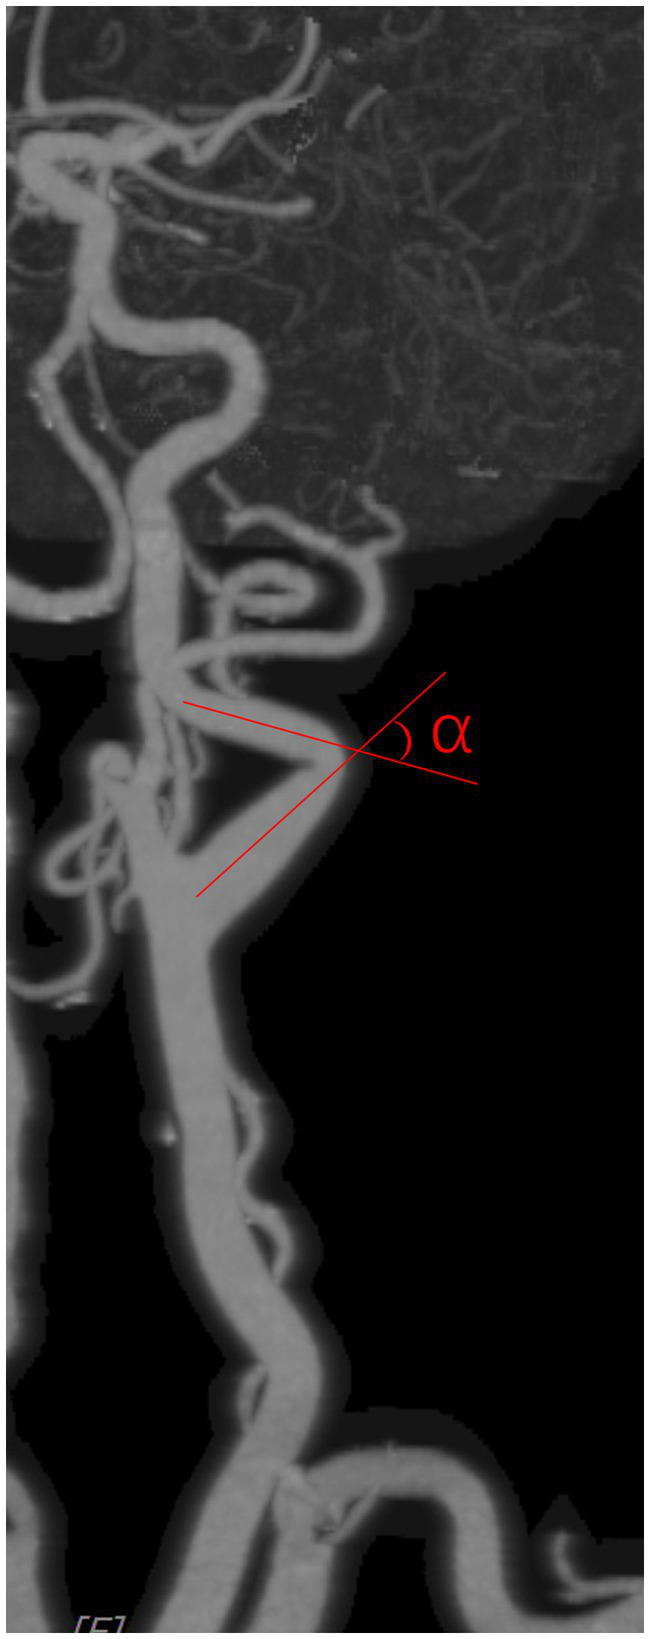

Carotid artery tortuosity refers to the angle between two adjacent segments of the carotid artery from the carotid bifurcation to the external orifice of the carotid canal being less than 150°, and it is identified as tortuosity if either side coincides. The carotid artery angle was measured as shown in Figure 2, with an imaginary line following the carotid path at each coiled or curve on a suitable view.

Figure 2

Figure 3

Carotid artery angle was measured as shown in the figure, with an imaginary line following the carotid path on a suitable view.